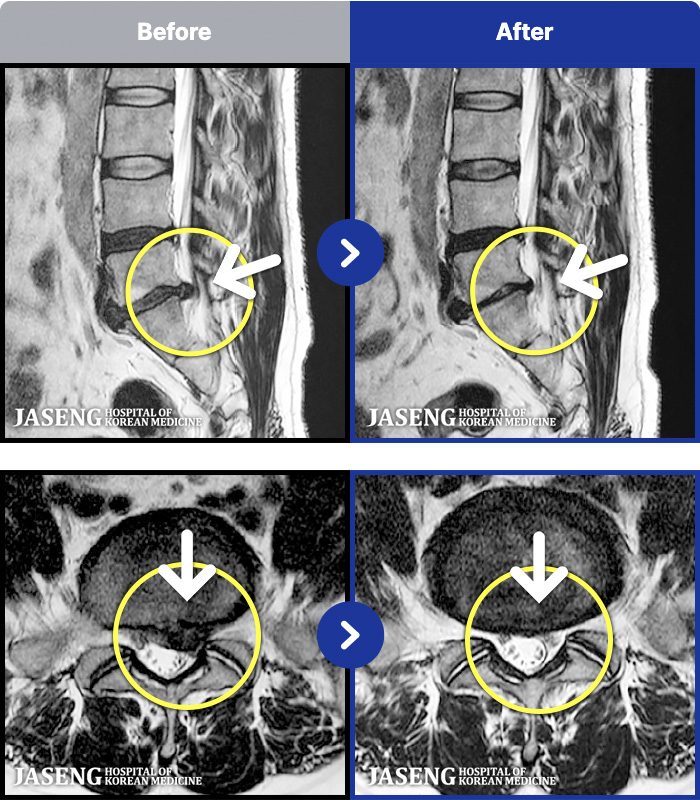

- MRI ġ

MRI ġ

1,240 MRI ũ ʸ Ȯϼ.